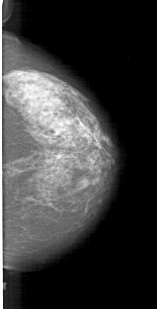

A_1632_1.RIGHT_CC

RIGHT_CC LINES 5866 PIXELS_PER_LINE 2971 BITS_PER_PIXEL 12 RESOLUTION 43.5 NON_OVERLAY